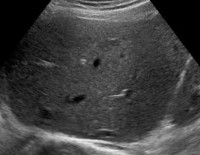

Ultrasound of the liver.

УЗИ печени. Диагностическое обследование выявляет строение печени, сосудов печени, желчного пузыря, желчных протоков. Используется как часть комплексного диагноза, он выявляет симптомы гепатита, ожирения печени, цирроза печени, желчнокаменной болезни, болезни Бадда-Киари, метастазов и рака печени. Существует несколько вариантов лечения: УЗИ печени, УЗИ печени + желчного пузыря, УЗИ печени + сосудистый допплер. Стоимость манипуляции зависит от ее сложности - чем больше структур проверено, тем дороже.

В норме печень имеет мелкозернистую структуру, умеренную яркость с равномерным распределением сигналов умеренной эхогенности. УЗИ назначают для уточнения диагноза с неоднозначной клинической картиной. На основании результатов процедуры выявляются следующие патологии:

УЗИ печени позволяет изучить строение и особенности функционирования организма: размеры, положение, строение отдельных долей. Полное ультразвуковое исследование печени и желчного пузыря позволяет нам оценить состояние печени, а также желчевыводящей системы - мочевого пузыря, печеночного протока и сфинктеров, отвечающих за продвижение желчи. УЗИ печени в сочетании с допплерографией сосудов и структурой самого органа отражает состояние кровотока, целостность и толщину стенок сосудов, диаметр просвета и извилистость артерий, вен и капилляры.В норме печень имеет мелкозернистую структуру, умеренную яркость с равномерным распределением сигналов умеренной эхогенности. УЗИ назначают для уточнения диагноза с неоднозначной клинической картиной. На основании результатов процедуры выявляются следующие патологии: